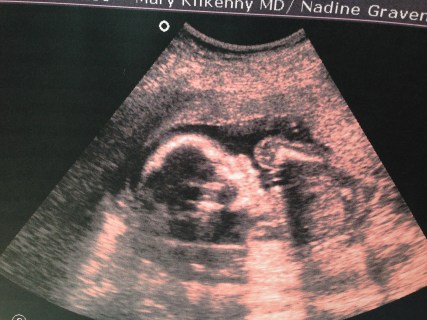

Shortly after we arrived at the hospital, my OB (Dr. Kilkenny–she’s Irish and I love her and would truly like to be her friend) arrived. Mondays are typically her day off, and she had just gotten up to meet with her personal trainer when she got the call to come straight to the hospital instead. Over the past year I’ve developed a strong relationship with Dr. Kilkenny–we’ve been through a lot together–and I was so glad that she was there to be the one delivering our baby.

While a nurse and Jon took Hannah next door to clean her up and take her vitals, the doctors completed my surgery and got me stitched up. It was then that I learned Hannah had been Frank Breech in my womb, basically doing a gymnasts pike position instead of diving head-down ready for delivery. She almost certainly would not have been born naturally. I was grateful all over again that I decided to stick with our plan for a repeat C-section and hadn’t changed my mind last-minute to give V-BAC another try!